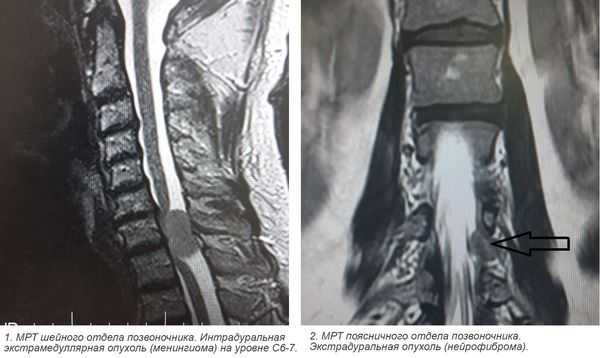

Учитывая темп развития симптомов, был заподозрен злокачественный характер опухоли. В день поступления (02.03.16) пациентке выполнена МРТ головного мозга и спинного мозга с контрастным усилением. Была выявлена диссеминация процесса с появлением опухоли в левом внутреннем слуховом проходе, множественных очагов патологического накопления контрастного вещества оболочек спинного мозга. Динамика распространения первичного очага и метастазирование представлены на рис. 1 и 2.

Рис 2. МРТ от 02.03.2016 - метастазирование опухоли по оболочкам спинного мозга (указаны стрелками).